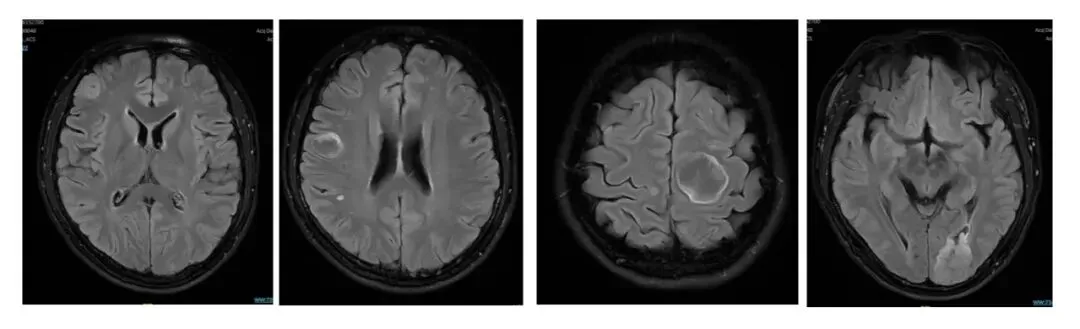

患者邹某某,2025年12月19日因“诊断肺恶性肿瘤1月余,头晕头痛 2日”就诊我院肿瘤内科。影像学检查显示双侧大脑半球多发占位性病变,考虑多发转移瘤。经充分讨论分析后,拟行颅脑转移灶 HyperArc 放疗。

[放影像学图片]